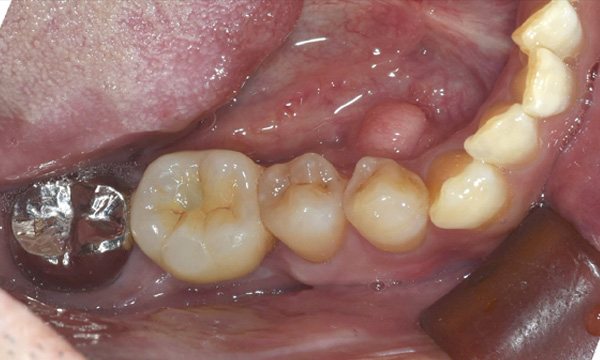

| 年代・性別 | 50代 男性 |

|---|---|

| 主訴 | 右下の歯がないのでインプラントをして欲しい |

| 治療期間 | 約6ヶ月 |

| 費用 | 600,000円 |

| 治療内容 | インプラント、骨造成、結合組織移植、セラミック修復 |

| 治療に伴うリスク | インプラント周囲炎 セラミックの破折、脱離 |